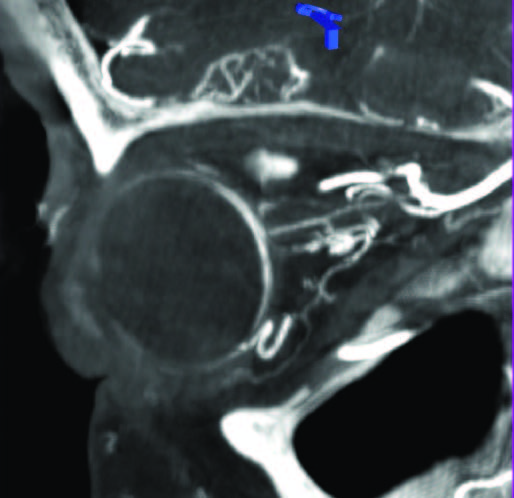

Рис. 2. Интранодальная паховая ПДКТ-лимфангиография с последующей чрескожной пункцией лимфопсевдоаневризмы (толстая красная стрелка) иглой 25 G (0,5 мм) (тонкие желтые стрелки) с целью эмболизации массивной послеоперационной тазовой лимфореи (длинная синяя стрелка): ПДКТ позволяет отчетливо визуализировать пункционную иглу на реконструированных изображениях и точно определить положение ее дистальной части.